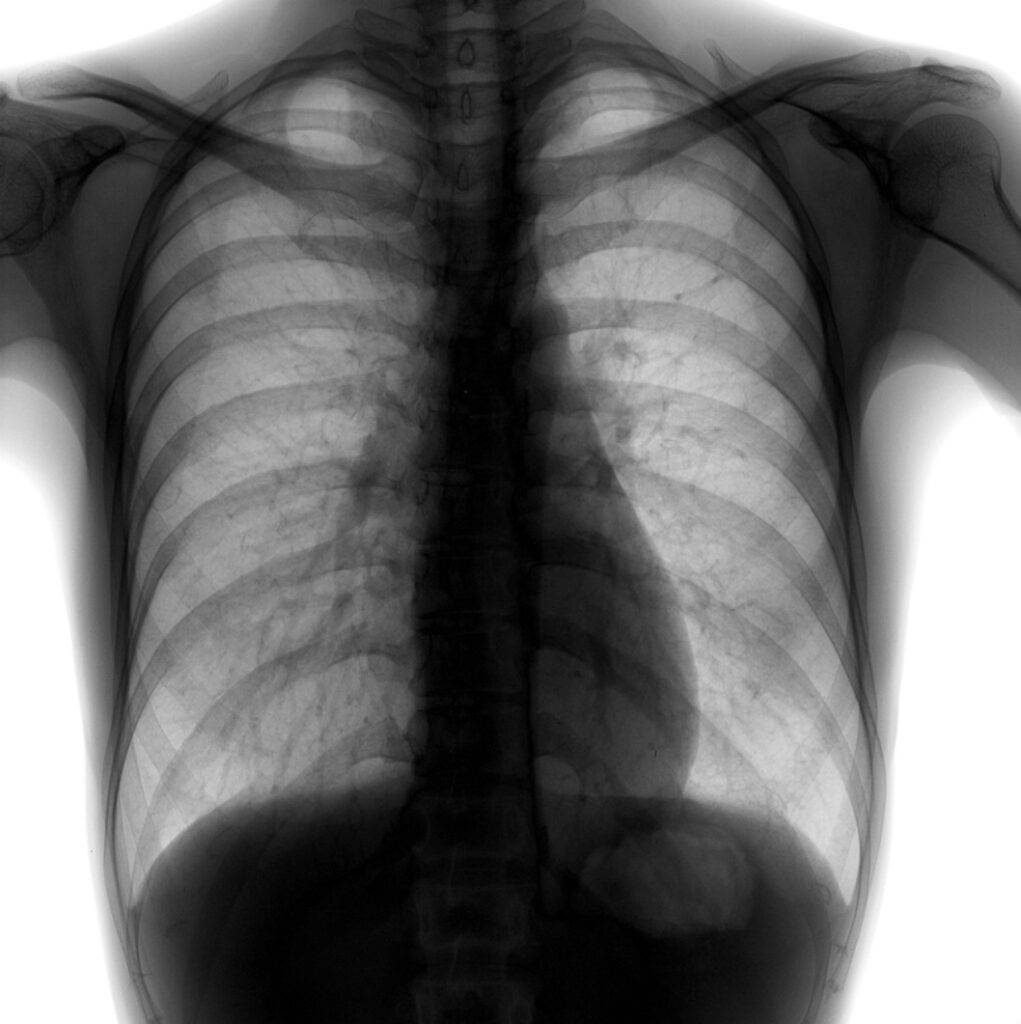

A Radiologia Convencional agora é digital ! Isso implica muitas vezes na facilitação dos trabalhos com equipamentos mais modernos, imagens mais claras e potencialmente mais diagnósticas, mas não esqueça da proteção radiológica. Ainda usamos raios X !!!